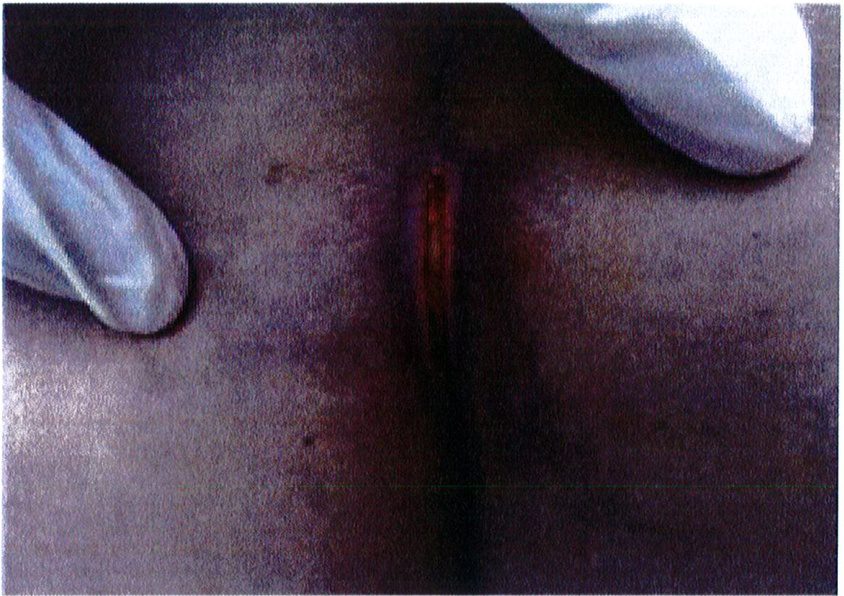

Theo kinh nghiệm của tác giả, nhiễm trùng lớp bề mặt và hoặc bục chỉ vết mổ là hai biến chứng thường gặp nhất (Hình 6). Nếu bục chỉ ở các lớp bề mặt thì có thể chăm sóc tại chỗ, làm sạch vết mổ và chờ liền. Còn trong trường hợp nặng, có thể thấy các tổ chức sâu phía bên dưới thì cần chăm sóc đặc biệt, thay băng và làm sạch vết mổ thường xuyên cho tới khi thấy được mô hạt sạch trên vết mố. Sau đó nên đóng vết mổ theo hai kỳ, kỳ đầu là lớp sâu, kỳ sau là lớp nông và cách nhau môt tuần.

Hình. 6. Bục chỉ vết mô